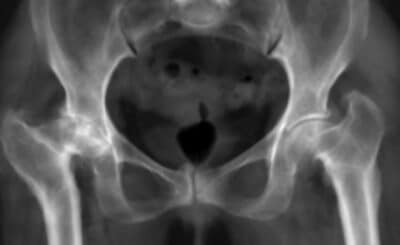

Implanting a hip prosthesis in coxopathy with normal radiographs

The most common procedure in hip surgery is primary total hip replacement for advanced hip osteoarthritis. In typical ca...